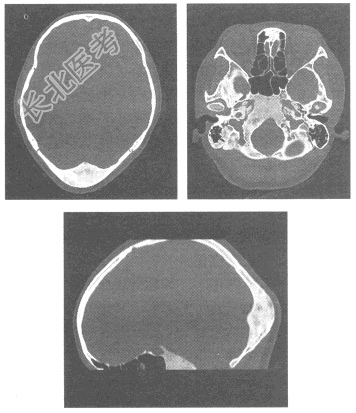

- 单项选择题男,41岁, 后枕部不适1个月余。根据CT平扫片,最可能的诊断为

A、脊索瘤

B、骨瘤

C、骨转移瘤

D、骨纤维异常增殖症

E、骨嗜酸性肉芽肿